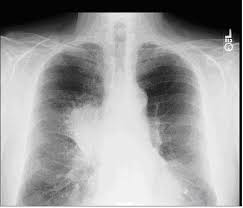

Since it affects your respiratory system, common symptoms associated with this disease are related to such conditions affecting the respiratory illness.

• Pneumonia or other respiratory infections, etc